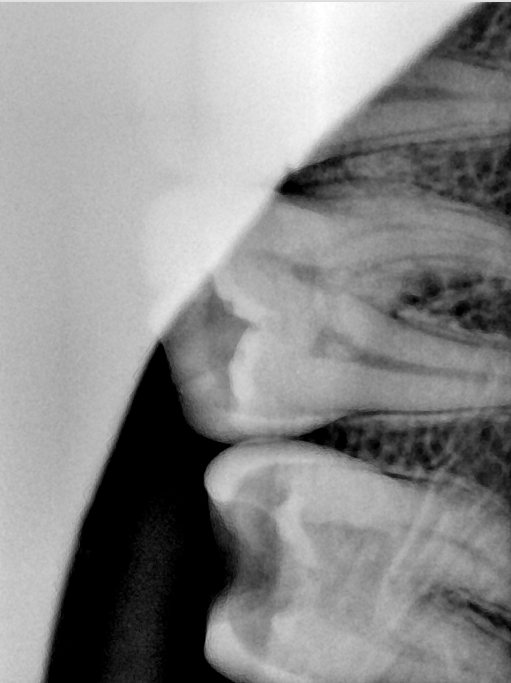

CR/DR 牙齿分割阶段记录

当前进展

- 完成了 CR/DR 牙齿相关分割训练

- 当前结果已经达到阶段预期,但仍有细节问题需要继续处理

相关测试

遇到的问题

- 训练过程中出现过 mask 下移问题

- 部分结果会出现 box 填充异常

- mask 边缘仍然有比较明显的锯齿感

参考